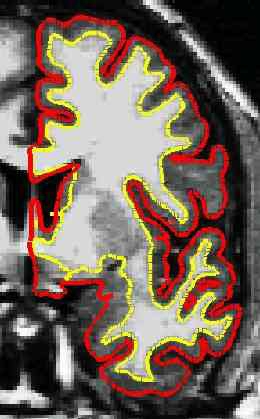

Only a few millimeters thick, the cortical layer contains the neurons and connections that comprise much of the brain’s workforce, but it appears abnormally thin in schizophrenia. Scientists debate whether the thinning marks a worrisome driver of pathology, a harmless byproduct of mental illness, or something else entirely.